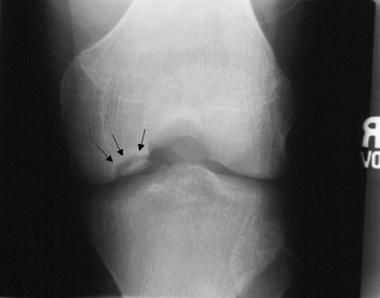

Основным методом инструментальной диагностики является рентген коленных суставов в двух проекциях, который позволяет увидеть структурные изменения бугристости [4] .

Фрагментацию с отрывом костного фрагмента лучше всего видно на боковой рентгенограмме [10] .

Рентгенологически отмечается характерная картина для этого заболевания. У молодых людей, когда еще не закрылась зона роста, видны неслившийся апофиз бугристости и отдельные костные фрагменты. Часто можно видеть значительную деформацию бугристости в виде «хобота». У более старших танцовщиков эта бугристость может иметь вид отдельных костных фрагментов.